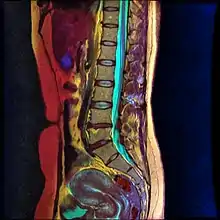

Lumbar sympathetic neurolysis is performed by using absolute alcohol, but other chemicals such as phenol, or other techniques such as radiofrequency or laser ablation have been studied. To aid in the procedure, fluoroscopy or CT guidance is used. Fluoroscopic guidance is the most frequent, giving better real-time monitoring of the needle. The general technique of administering lumbar sympathetic neurolysis involves using three separate needles rather than one because it allows for better longitudinal spread of the chemicals.[6]